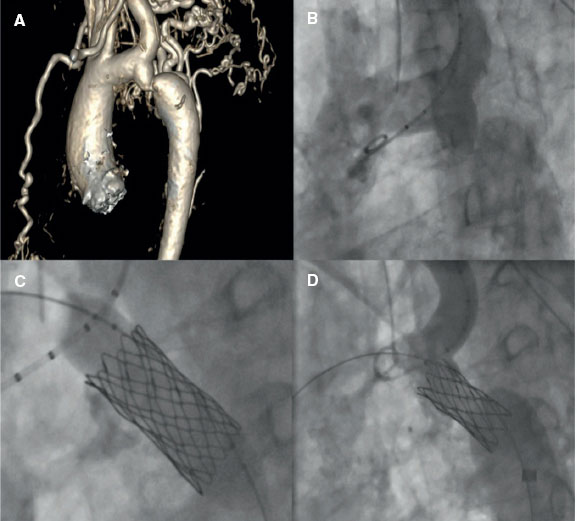

Adequate planning will be crucial in ensuring better outcomes and minimizing the risk of complications associated with coarctation stenting. Several steps may coincide with the BA. The main steps and technical considerations will be addressed below. Figure 2 illustrates a case of an AC successfully treated with stent implantation.

Figure 2. A successful treatment of aortic coarctation in an adult. A: computerized tomography showing aortic coarctation. B: angiography confirming aortic coarctation. C: balloon angioplasty and stent implantation. D: final fluoroscopic result after stent implantation.